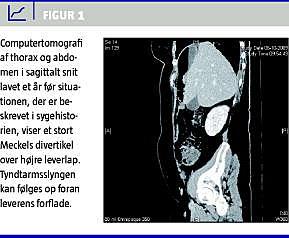

Et år tidligere havde patienten henvendt sig med et lignende, men mildere symptombillede og fik under denne indlæggelse foretaget computertomografi af abdomen (Figur 1 ). Her sås en tarmanomali tydeligt, og tyndtarmen kunne følges fra sin normale position i midtabdomen med et slankt tarmstykke op forbi leverens forflade til et stort divertikel under højre diafragmakuppel. Dengang blev divertiklet radiologisk tolket som tyktarm og dermed som udtryk for Chilaiditis syndrom, hvor colon er interponeret mellem diafragma og højre leverlap. Tilstanden findes hos op til 1% af en geriatrisk population. Symptomerne er abdominale smerter, distension og natligt opkast og indicerer ikke umiddelbart laparotomi [4]. Patientens smerter gik i sig selv, og videre opfølgning blev skønnet unødvendig, da hun i efterforløbet var anfaldsfri.